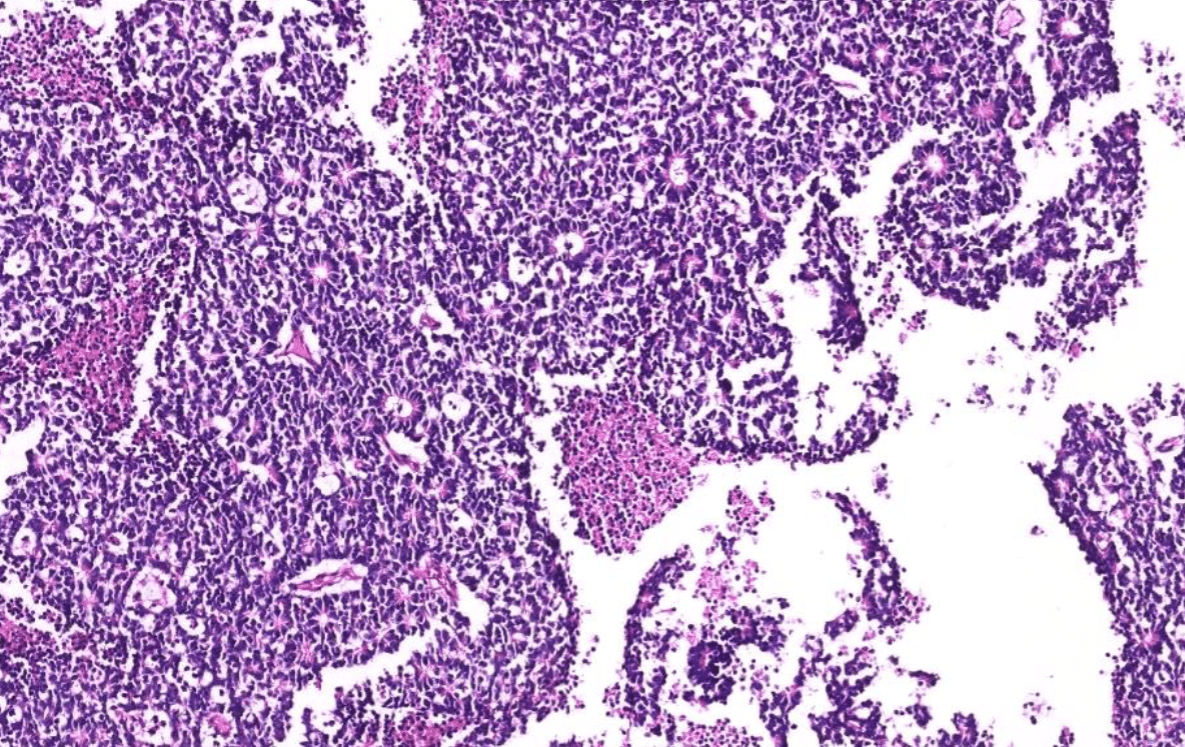

lung adenocarcinoma